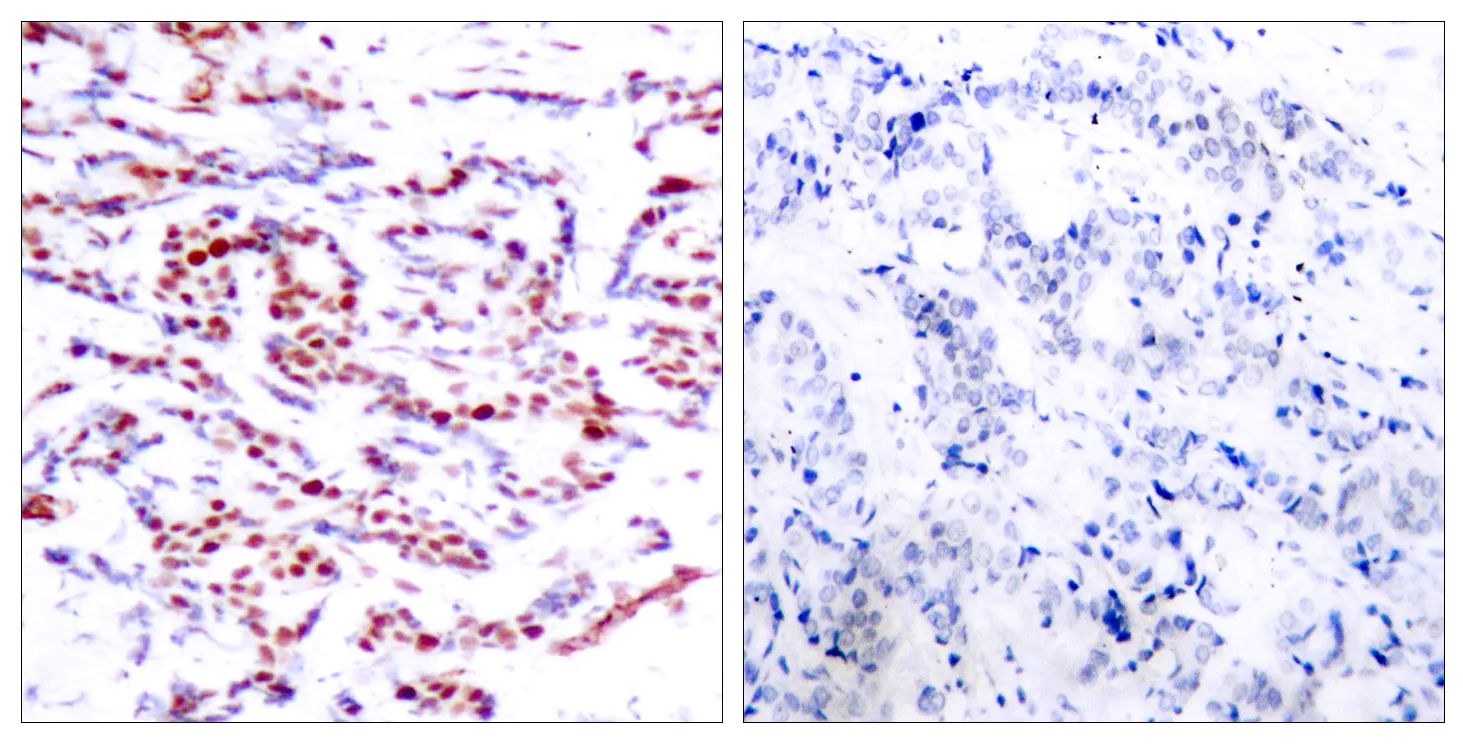

ATF-2 (phospho Thr71) Rabbit Polyclonal Antibody

Cat: APRab04278

Size1:50μl Price1:$128

Size2:100μl Price2:$230

Size3:500μl Price3:$980

Size2:100μl Price2:$230

Size3:500μl Price3:$980